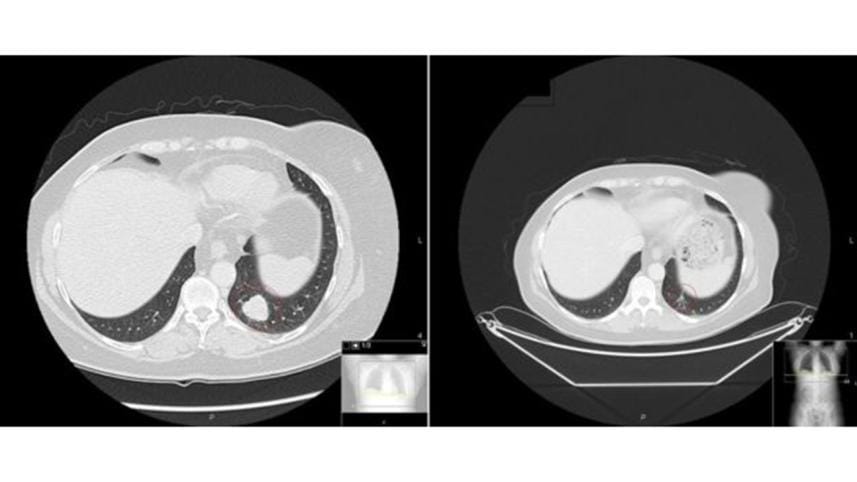

Vicky Brown, 61 and from Cardiff, was diagnosed with malignant melanoma that had spread to her lungs and breast in April 2013.

She started the combination therapy later that year.

"It worked within a month. There were lumps I could actually feel and they disappeared quite quickly," she told the BBC.

She did face severe side effects including an upset liver and inflamed bowels and a year later the cancer returned.

She is now on her second course of combination immunotherapy, which again seems to have shrunk the tumours.